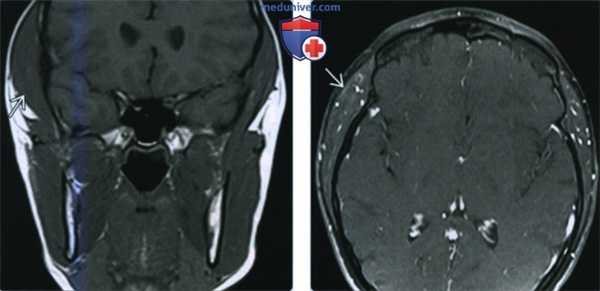

(Справа) Фото пациента с доброкачественной односторонней гипертрофией жевательной мышцы. Обратите внимание на значительное выбухание правой щеки, обусловленное гипертрофией жевательной мышцы. (Слева) При МРТ Т1ВИ в коронарной проекции отмечается увеличение правой височной мышцы у пациентки, обеспокоенной косметическим дефектом, который становится заметным при забранных в хвост волосах. И хотя чаще встречается гипертрофия жевательной мышцы, увеличиваться в размерах может и любая другая мышца.

(Справа) При МРТ Т1FS с КУ в аксиальной проекции у этой же пациентки сигнал от увеличенной мышцы имеет нормальную интенсивность, контраст не накапливается.

(Слева) При МРТ Т1ВИ в коронарной проекции отмечается увеличение правой височной мышцы у пациентки, обеспокоенной косметическим дефектом, который становится заметным при забранных в хвост волосах. И хотя чаще встречается гипертрофия жевательной мышцы, увеличиваться в размерах может и любая другая мышца.